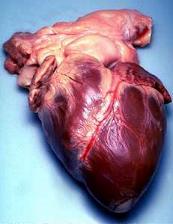

القلب Heart عضو عضلي يضخ الدم في جسم الإنسان. ومع كل دقّة يدفع القلب الدم الضروري للحياة عبر جسم الإنسان. ويحمل الدم الأكسجين والغذاء لكل خلايا الجسم وتبدأ دقات القلب ذات الإيقاع المنتظم قبل سبعة أشهر من ميلاد الطفل تقريبًا. وعندما يتوقف القلب تتوقف الحياة، إلا إذا ساعدت أجهزة آلية خاصة على دوران وأكسجة الدم. والقلب عضو عضلي مجوّف كبير، ينقسم إلى مضختين متجاورتين. وتنقل الأوردة الدموية الدم في جميع أنحاء الجسم إلى المضخة الواقعة في الجهة اليمنى التي ترسله بدورها إلى الرئتين لحمل الأكسجين، ومن ثم، ينساب الدم المؤكسد إلى الجهة اليسرى من القلب التي تضخه إلى أجزاء الجسم المختلفة بوساطة الشرايين. وهناك صمامات تتحكم في سريان الدم داخل القلب. والمضخة اليسرى، التي تدفع الدم إلى جميع أنحاء الجسم أقوى وأكبر حجمًا من المضخة اليمنى. والقلب والتشكيلات الأنبوبية الأخرى مثل الشرايين والأوردة والشعيرات تسمى جميعًا الجهاز الدوري أو الجهاز القلبي الوعائي. ينظم الجهاز العصبي عمل القلب وأجزاء أخرى من الجهاز الدوري. وينظم الجهاز العصبي التلقائي، وهو جزء من الجهاز العصبي، ضربات القلب (النبض)، فيقللها أو يزيدها حسب حاجة الجسم؛ لذلك فإن القلب يدق بصورة هادئة مثلاً عندما يكون الإنسان نائمًا ويزود الجسم بكمية قليلة نسبياً من الأكسجين. وقد تزداد سرعة ضربات القلب مرة أخرى لتزيد كمية مردود الأكسجين للجسم بغزارة. ويحدث هذا عندما يزاول الإنسان التمارين الرياضية أو عندما يصاب بالخوف أو عندما يحتاج للمقاومة أو العراك أو الجري. وقد يصيب المرض أو الخلل أي جزء من أجزاء القلب أو الأوعية الدموية، ويعتبر ذلك من الأسباب الرئيسية للوفاة في البلدان الصناعية. وأكثر أمراض القلب شيوعًا هي التي تصيب الشرايين التي تغذي القلب نفسه بالدم. والخلل الذي يصيب هذه الشرايين قد يتطور مع سنوات عمر الإنسان. فترسُّب المواد الدهنية مثلاً، يؤدي إلى انسداد شرياني وإلى قلة كمية الدم التي تزود القلب. وإذا استقبلت عضلة القلب كمية قليلة من الدم فإن هذا قد يؤثر في أدائها أو إلى موتها. ويسمى هذا الخلل أو التلف الناتج من قلة إمداد عضلة القلب بالدم النوبة القلبية. والنوبة القلبية الخفيفة قد تجبر الإنسان لكي يعيش حياة أقل نشاطًا وحركة. أما النوبة القلبية القاسية أو العنيفة فتجعل القلب غير قادر على إمداد الجسم بكمية كافية من الدم، حتى في حالة الراحة الكاملة، وقد تؤدي إلى الوفاة. وقد تصيب الأمراض أجزاء أُخرى من القلب وقد يؤدي هذا إلى تأثير مدمّر مشابه. تحققت أهم التطورات الطبية الحديثة في مجال طب القلب، وهو حقل طبي يعنى بالأمراض التي تصيب القلب والأوعية الدموية. ومنذ آلاف السنين، لم يكن مرضى القلب يعرفون أصلاً أن لهم هذه المشكلة. وفي التسعينيات من القرن العشرين الميلادي، تعلم الأطباء كيف يشخصون ويعالجون بعض حالات مرض القلب التي كان علاجها علاجها مستحيلاً في السابق، وكانت تعني الوفاة لمن يصاب بها. وأدّى اكتشاف الأدوية والتطور الهائل في الجراحة إلى إعطاء عدد من مرضى القلب أملاً في الحياة، وبدأ الأطباء بزراعة القلوب بل طوّروا أجهزة تقوم بعمل القلب مؤقتًا. واليوم تُجرى كثير من الأبحاث في علم القلب ووظائفه، ويتم التركيز على دراسة الأسباب التي تؤدي إلى أمراض القلب حتى يمكن تفاديها. وتدرس أبحاث أخرى إمكانية خفض حالات الموت والعجز التي تنتج من أمراض القلب، عن طريق دعم وتطوير أدوية وعقاقير معالجة جديدة واستحداث قلب صناعي فعّال. هذه المقالة عن قلب الإنسان بصورة خاصة، والجزء الأخير منها يصف قلب الحشرات والسمك والطيور والحيوانات الأخرى. ولمزيد من المعلومات عن عمل الدم في الجسم،

صفات تشريحية

وزن القلب يبلغ 0.5% من وزن جسم الإنسان أي أنه بحدود 350 جرام لشخص يزن 70 كج ويمكن لهذا الوزن أن يزداد بزيادة عمله كما عند الرياضيين. يترافق هذه الزيادة الوزنية بازدياد حجم الدم الذي يضخ في النبضة الواحدة فما يزداد عند الرياضيين هو كمية الدم التي تضخ وليس عدد النبضات.

يتكون القلب بصورة أساسية من عضلة تسمى عضلة القلب أو عضل القلب، التي تكوِّن جدار القلب والحاجز الذي يفصل بين الجانبين الأيمن والأيسر للقلب. وكل عضلات القلب تنقبض وتتمدد وتدفع الدم عبر القلب. يغطي القلب من الخارج غشاء يسمى النخَاب ويحيط غشاء آخر يسمى التّامور بالنخاب وبالقلب بصورة تامة وكاملة، ويمتد حتى أعلى القلب ليشمل الأوعية الدموية الممتدة أعلى القلب. وتوجد مادة لزجة بين التامور والنِخَاب تساعد القلب على الانقباض بسهولة. تختلف عضلة القلب عن عضلات الجسم الأخرى مثل العضلة الملساء والعضلة الهيكلية. فالعضلات الهيكيلية مثل التي في الذراع أو الرِجل لها ألياف طويلة وشرائح داكنة اللون وأخرى فاتحة بالتبادل، ويسمى هذا بالتخطُّط. ونحن نستطيع أن نتحكم في العضلة الهيكلية. أما العضلات الملساء التي تكون جدار المعدة الداخلي والأمعاء ومعظم الأعضاء الداخلية للجسم فخالية من التخطط وتعمل بحركة تلقائية ولا نستطيع أن نتحكم فيها. وعضلات القلب لها تخطُّط مثلها مثل العضلات الهيكلية. ولكنها تنقبض وتتمدد بحركة تلقائية مثل العضلات الملساء. وبالإضافة لذلك فإن خلايا عضلات القلب تعمل مجتمعة وكأنها خلية واحدة. فعندما تنقبض أو تتمدد أي خلية في القلب فإن الخلايا المحيطة بها تعمل الشيء نفسه، ولهذا السبب يخفق القلب أو يدق دائمًا وبانتظام مدة حياة الإنسان.